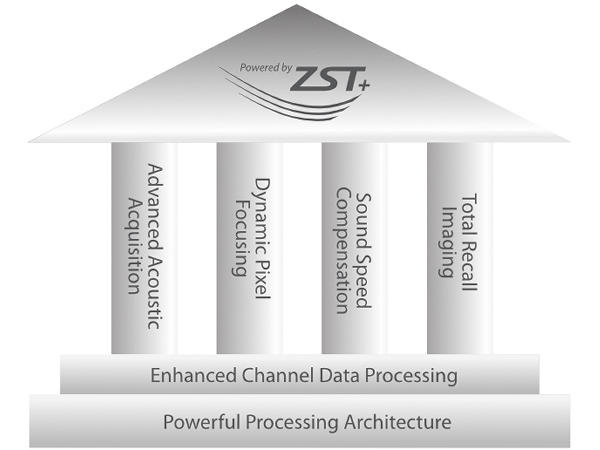

Powered by ZST +

The ZST + platform represents an extraordinary leap forward in ultrasound technology, moving away from traditional beam-forming to channel data processing. This groundbreaking innovation overcomes the traditional trade-offs among spatial resolution, temporal resolution, and tissue uniformity, resulting in unparalleled image quality that empowers infinite imaging solutions.